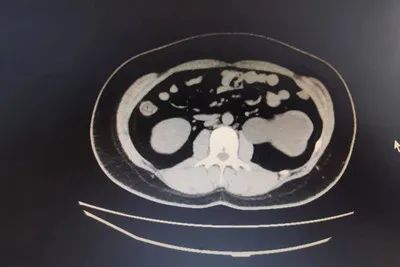

泌尿系CT及逆行造影检查,示:左肾重度积水、肾盂扩张,输尿管肾盂连接部以下无扩张积水,肾盂呈肾内型肾盂。